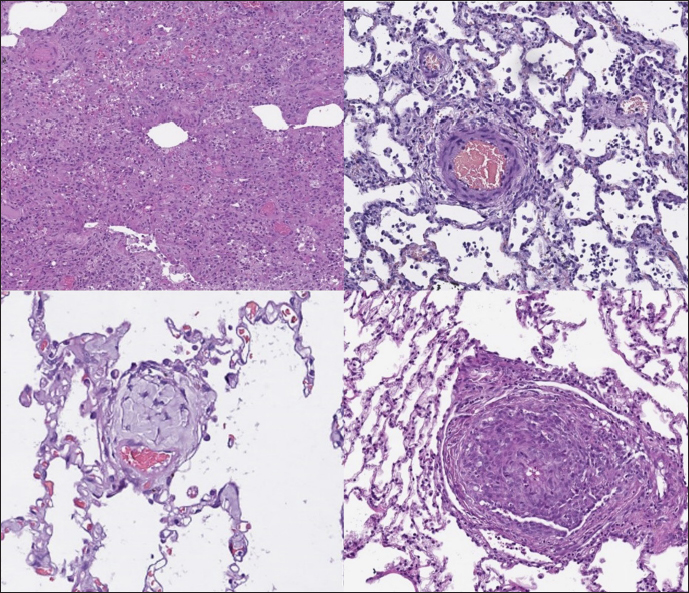

In the sPCH group, we found zones of multifocal mild-to-moderate alveolar septa thickening with numerous capillary proliferation with signs of congestion. Endothelial cells were flattened, but had no signs of anisocytosis or anisokariosis. The growing capillaries expanded in pulmonary tissue, forming nodules and web-like anastomosis with bizarre vessel proliferation which affects zonal bronchi and arteriolas (Figs. 4 and 5).

Fig. 4. sPCH group. Left (dog)—portions of alveolar septae with duplicated capillaries and capillaries proliferation into arterial walls. Right (cat)—less prominent septal alteration, significant arterial walls capillary proliferation. Stained with H&E.

Fig. 5. sPCH group. Net-like capillaries organization in alveolar septa (cat).